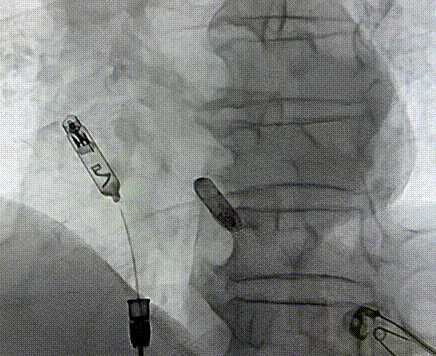

RAO 30°体位下,缓慢推送导管,直至保护套筒位于右心耳底部,使用解剖标记/猪尾导管造影确定右心耳的部位和右心耳的深度,当观察到“雨刷”摆动后停止推进;在透视下解锁保护套筒,保持起搏器不动,完全回撤保护套筒,观察到头端螺旋没有位移,且导管形态张力合适。

工程师进行定位标测(腔内图形、损伤、阻抗、感知、阈值),参数正常。在旋入固定之前,留存影像来记录机器“V形标记”的起始位置,缓慢顺时针旋转控制旋钮,旋入AVEIR™ AR器械过程中持续测试观察趋势,旋至1.5圈,进入对接栓模式;进行张力测试,整体轻微施加张力回撤导管,持续几个心动周期后将无导线起搏器返回松弛状态进行电学参数测试,参数稳定,完成心房无导线心脏起搏器植入。